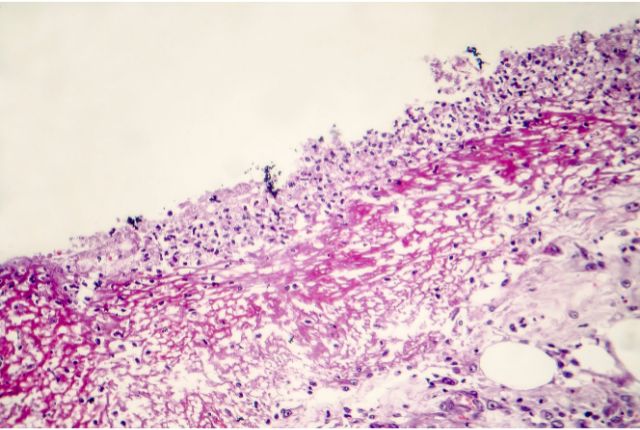

Ces agents infectieux colonisent la muqueuse intestinale et génèrent une inflammation très sévère des tissus. Cette inflammation de la muqueuse colorectale empêche les tissus de la paroi intestinale d’absorber l’eau, et conduit l’eau à être évacuée par les selles. D’où des selles très liquides, appelées diarrhées (selles non moulées, émises plus de trois fois par jour).

En outre, l’inflammation de la muqueuse entraîne peu à peu sa destruction : les fragments de tissu et du sang se retrouvent dans les selles. Dans les cas les plus sévères de dysenterie (soit dans 10 à 20 % des cas), l’inflammation peut conduire à la formation d’abcès purulents au niveau des poumons, du cerveau et du foie. En l’absence de prise en charge médicale, ces abcès peuvent être mortels.